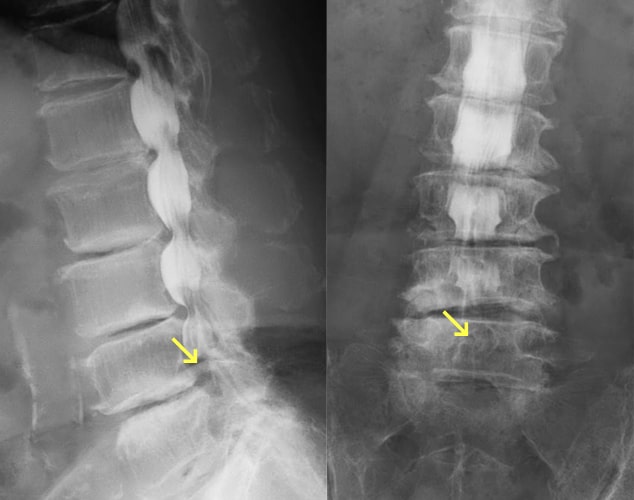

脊椎分離症とすべり症

疲労骨折などにより椎骨が椎弓の関節突起間部で分離したものを脊椎分離症といい、さらに分離した椎体が前方へ転位したものを脊椎すべり症といいます。日本人男性の約8%にみられ、成長期のスポーツ選手の腰痛の原因の30~40%を占めます。症状は腰部から臀部、大腿後面の痛み、背部・分離部の圧痛・叩打痛、神経性間欠跛行などです。治療法としては保存療法と手術療法がありますが、慢性期で痛みが強くない限りは手術は行わず保存療法となります。保存療法は、コルセットや体幹ギプスなどによる固定や運動の制限を急性期には行い、慢性期では薬物療法・分離部のブロック注射などの対症療法に加え、脊椎の負担のかからない動作や姿勢の指導、体幹筋のトレーニングを始めとした理学療法を行います。